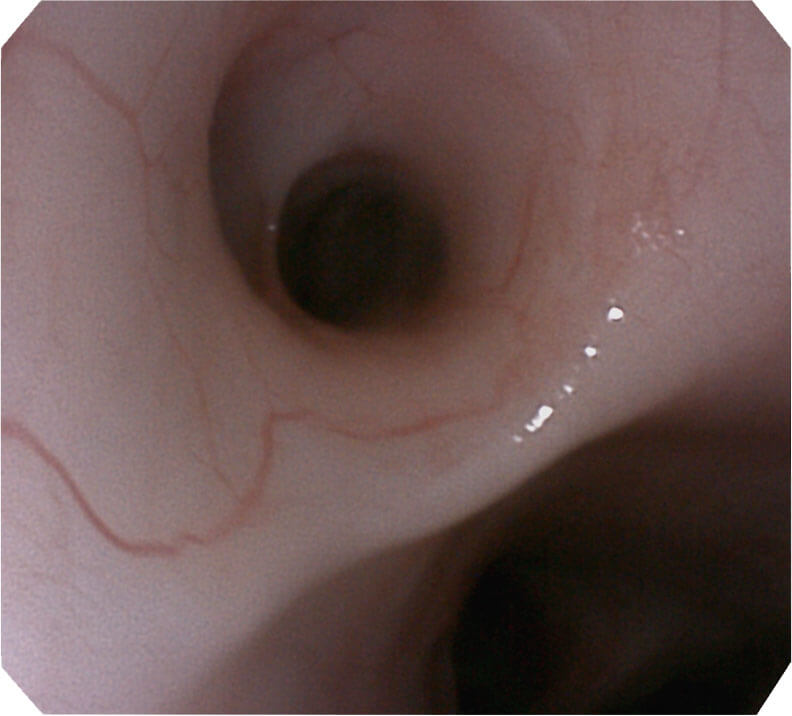

高分辨率画质

帮助医生更加清晰地观察气管表面病灶